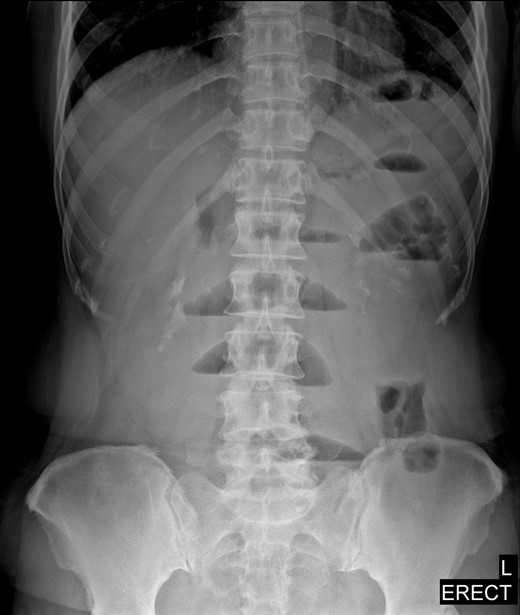

Laboratory data were unremarkable. Abdominal X-rays showed slight distension of small bowels with air-fluid levels (Fig. 1). CT scan revealed that dilated small bowel loops probably ileal level in left lower quadrant (Fig. 2). A nasogastric tube was inserted and she was given a conservative treatment over the next 2 days, but we proposed a laparoscopic exploration because of no clinical improvement.

Upright abdominal radiograph showing multiple air-fluid levels, suggestive of possible distal bowel obstruction.